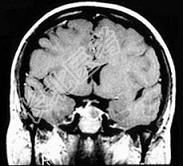

- 疑为垂体腺瘤时,定位诊断首选( )。A、